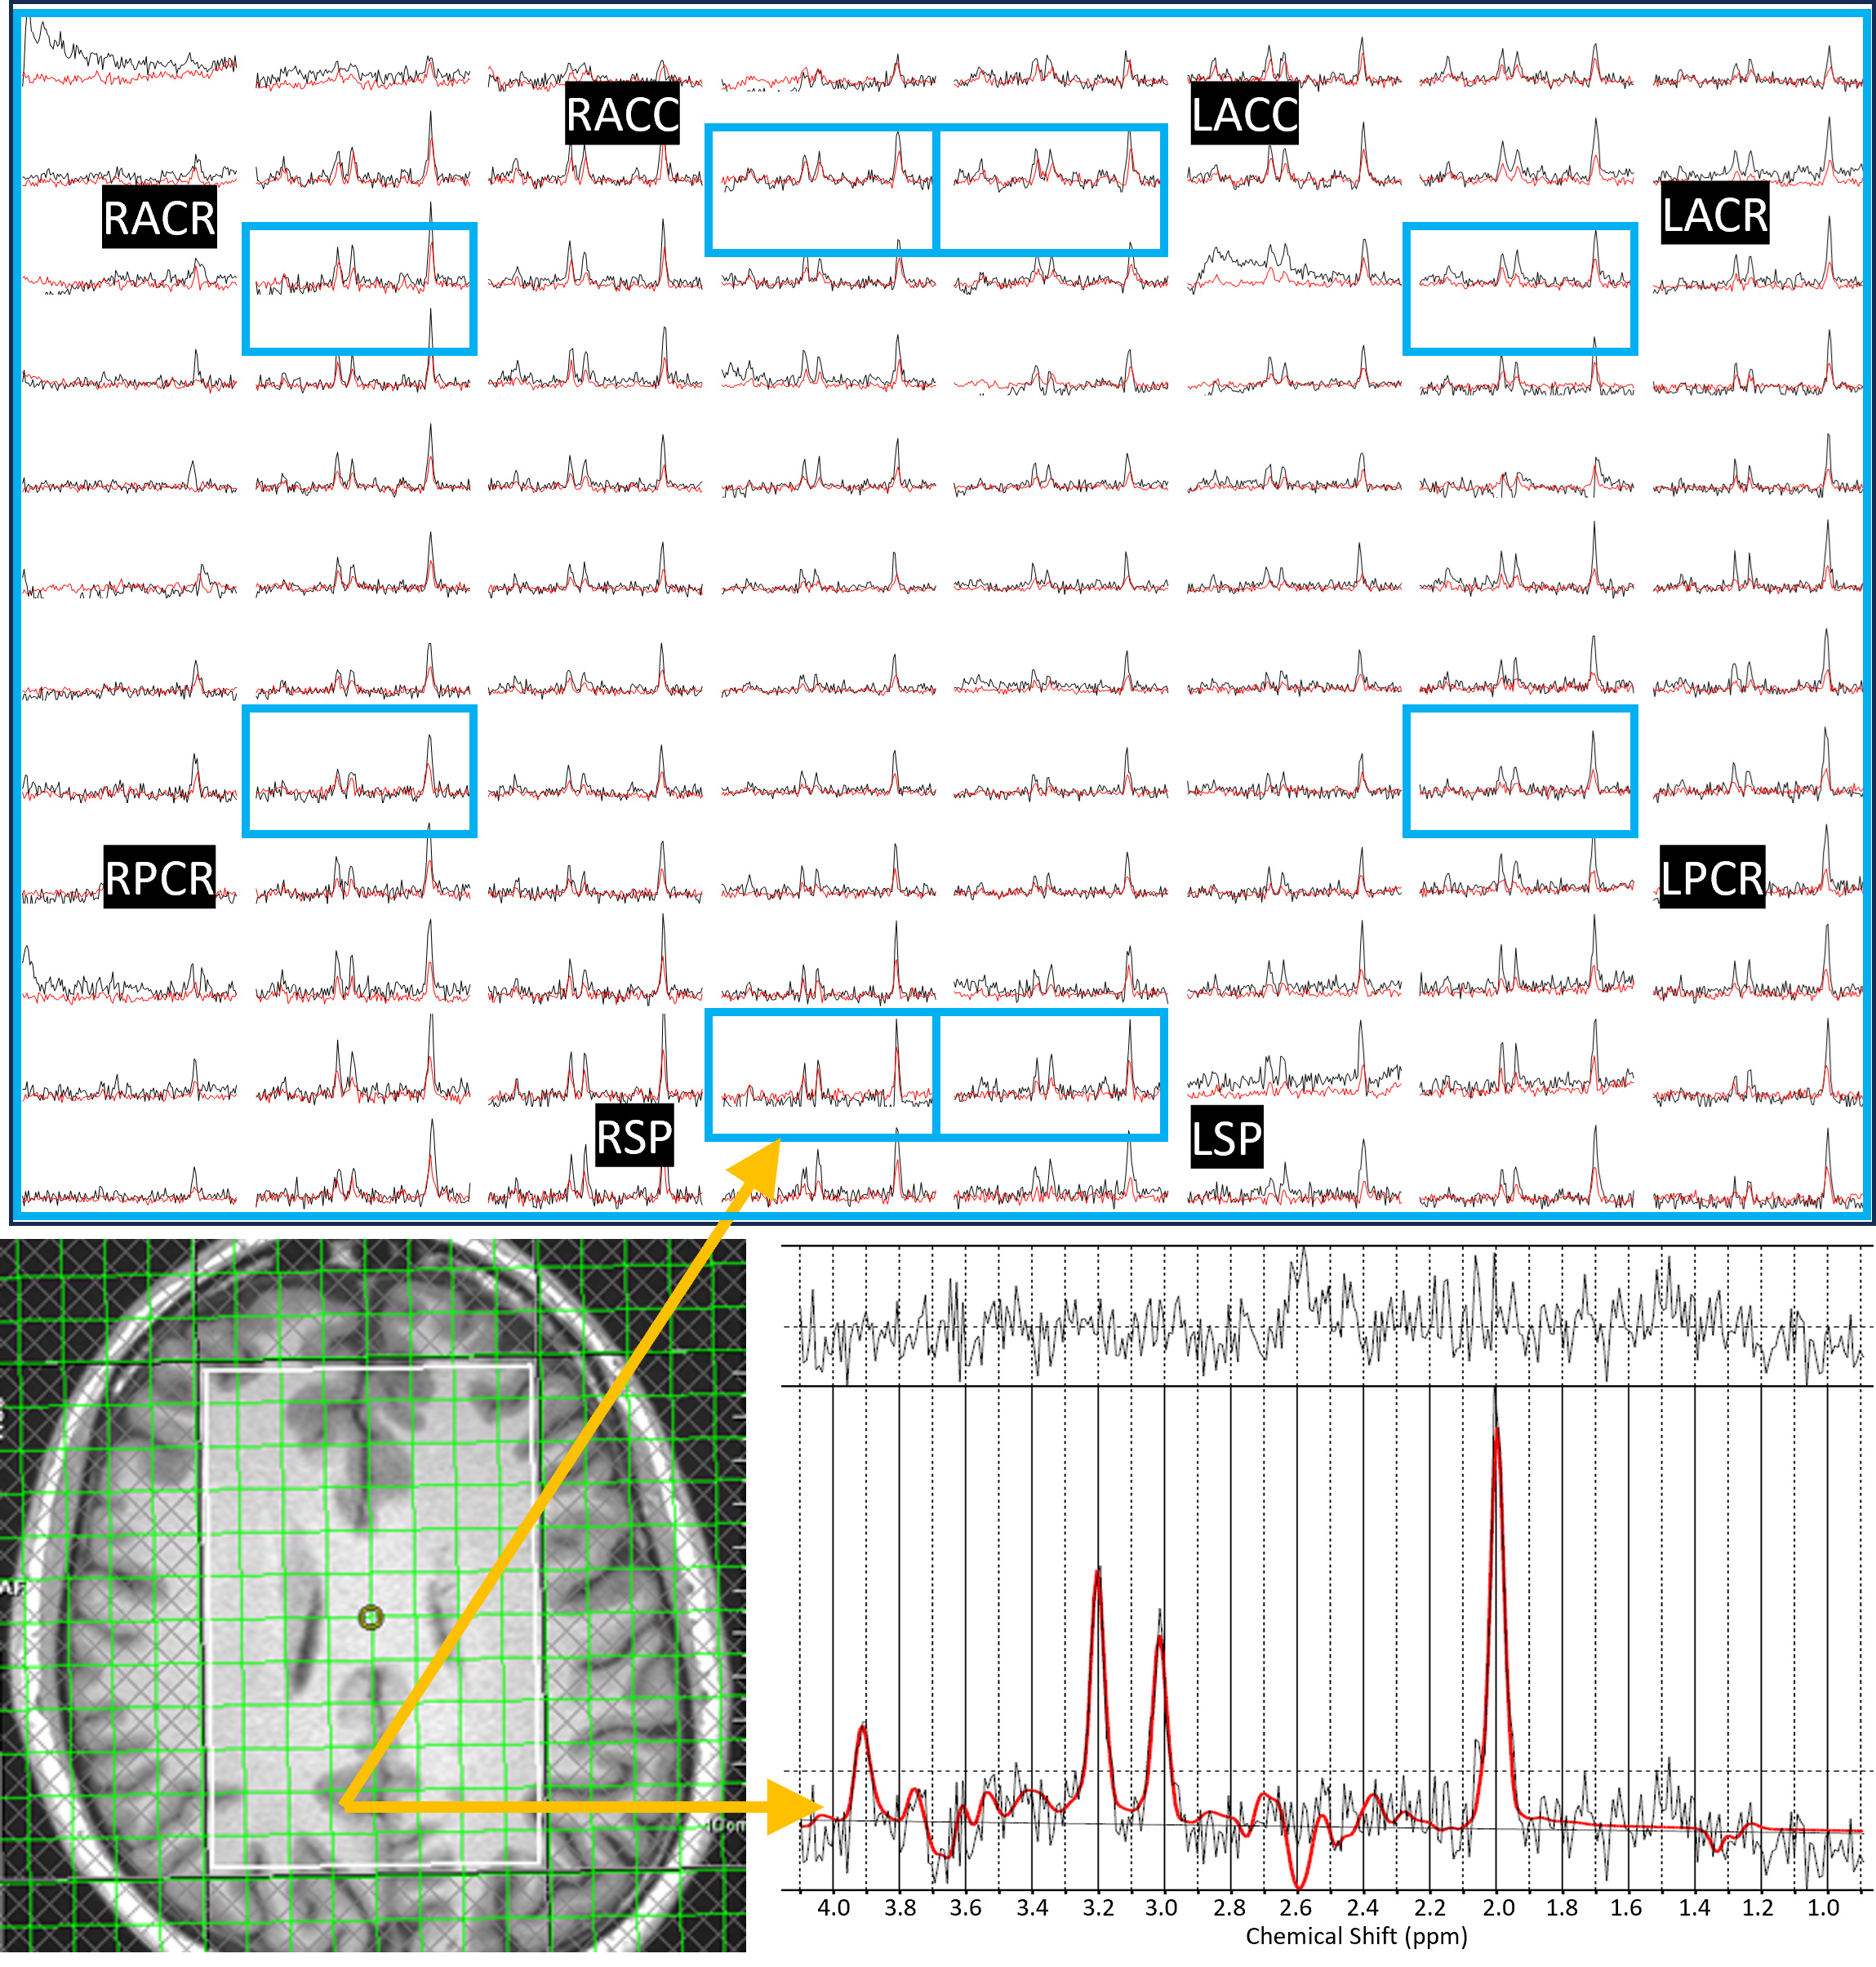

2.1. Trace-Weighted Single-Shot Diffusion Spectroscopic Imaging

2.4. Data Reconstruction and Post Processing

- Saucedo, A.; Thomas, M.A. Single-shot diffusion trace spectroscopic imaging using radial echo planar trajectories. Magn. Reson. Med. 2024, 92, 926–944. [Google Scholar] [CrossRef]